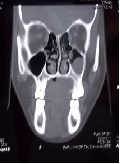

Multiple Accessory Mental Foramen: A Rare Anatomical Finding

Hakan Avsever*, Kaan Gunduz, Seda Ozgedık, Hilal Peker Ozturk,Savaş Ozarslanturk, Kaan Orhan